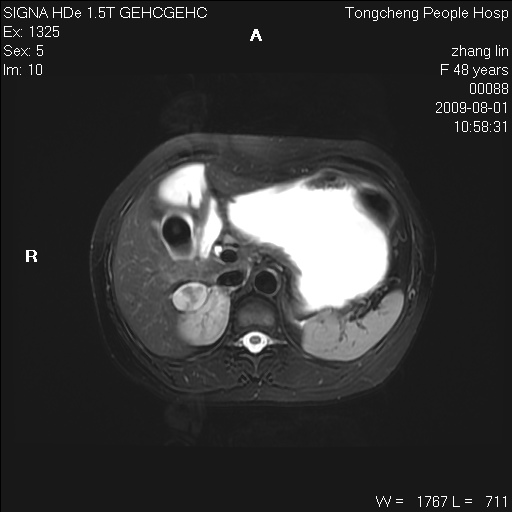

女,48岁。健康体检,彩超发现右肾占位性病变。平素健康。

临床诊断:右肾占位性病变,性质待定(囊肿?肿瘤?)。

上中腹部mr平扫+增强扫描,图像如下:

右肾上极见一类圆形病灶,t1wi呈等信号t2wi呈等高混杂信号,三期增强无强化,边界清---考虑囊肿出血。

同反相位均表现为等信号,病变无强化,考虑含蛋白的囊肿可能,弥散加权相或许有些帮助,